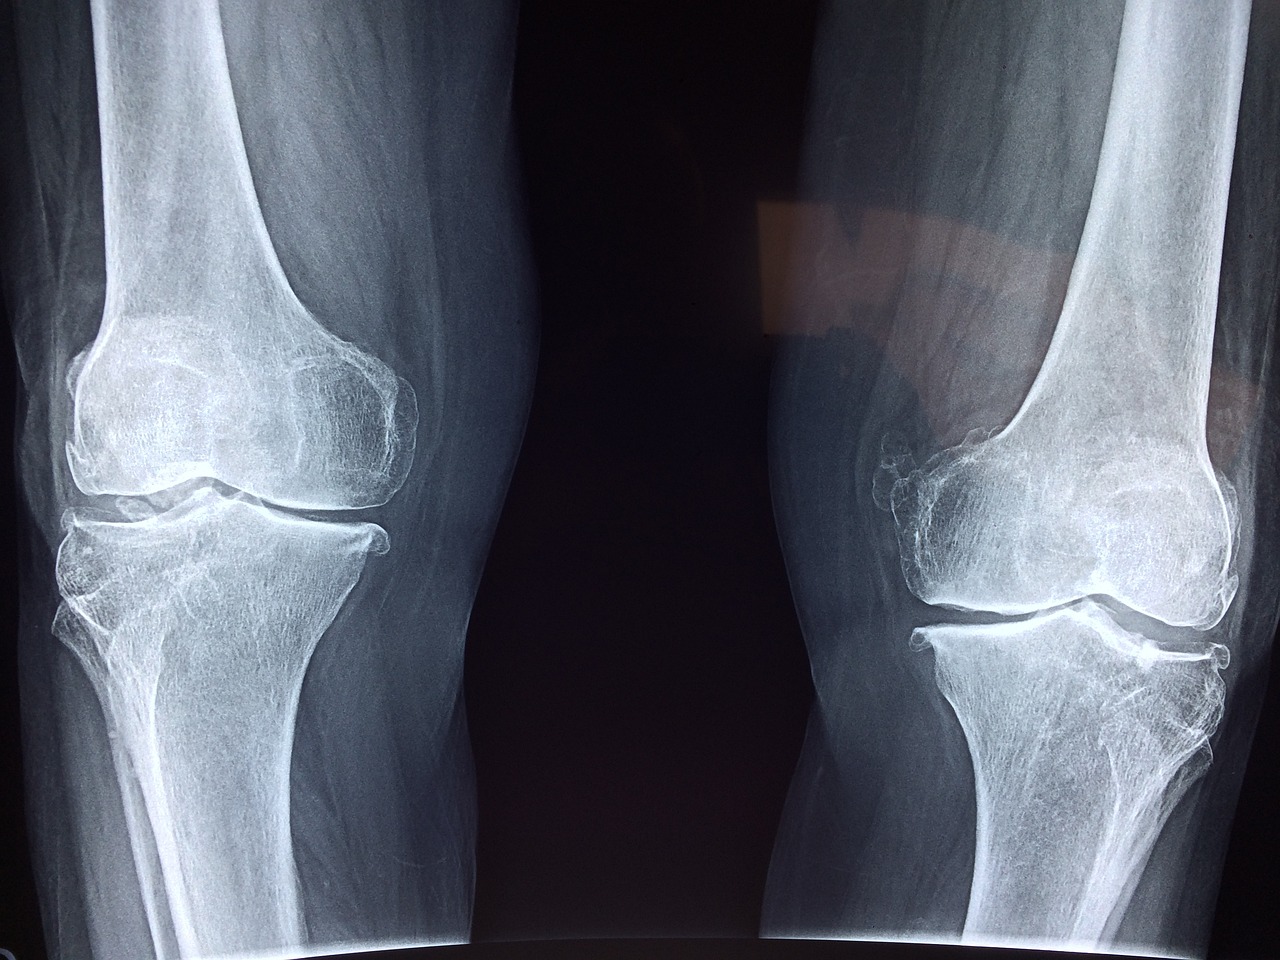

관절염은 관절 부위의 통증, 염증, 손상 및 기능 장애를 일으키는 만성적인 질환입니다. 관절염에 걸린 사람들은 일상 생활에서 어려움을 겪을 수 있습니다. 하지만, 올바른 식습관과 영양소가 풍부한 식품을 선택하는 것은 관절염 예방 및 관절 건강에 큰 도움이 될 수 있습니다. 이 글에서는 관절염 예방과 치료에 좋은 음식과 요리를 알아보겠습니다.